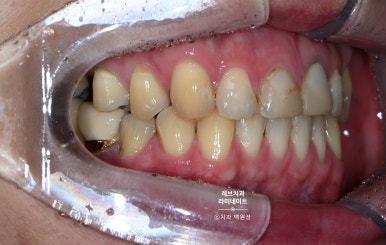

같은 사람임을 인증하기 위해서, 레브네이트 치료 받지 않은 어금니까지 보이는 사진을 첨부했습니다.

그리고 특별한 착시가 들어가 있는데요, 옆에서 보면 꽤나 송곳니가 넓어보이는 것을 확인하실 수 있을거에요. 심지어 좌우 사이즈도 좀 다르죠.

다만, 앞에서 보면 완전 대칭으로 보입니다! 앞에서 보이는 각도를 감안해서 만듦으로써 환자분이 갖고 있는 상황 내에서 최선의 결과를 내는 것.